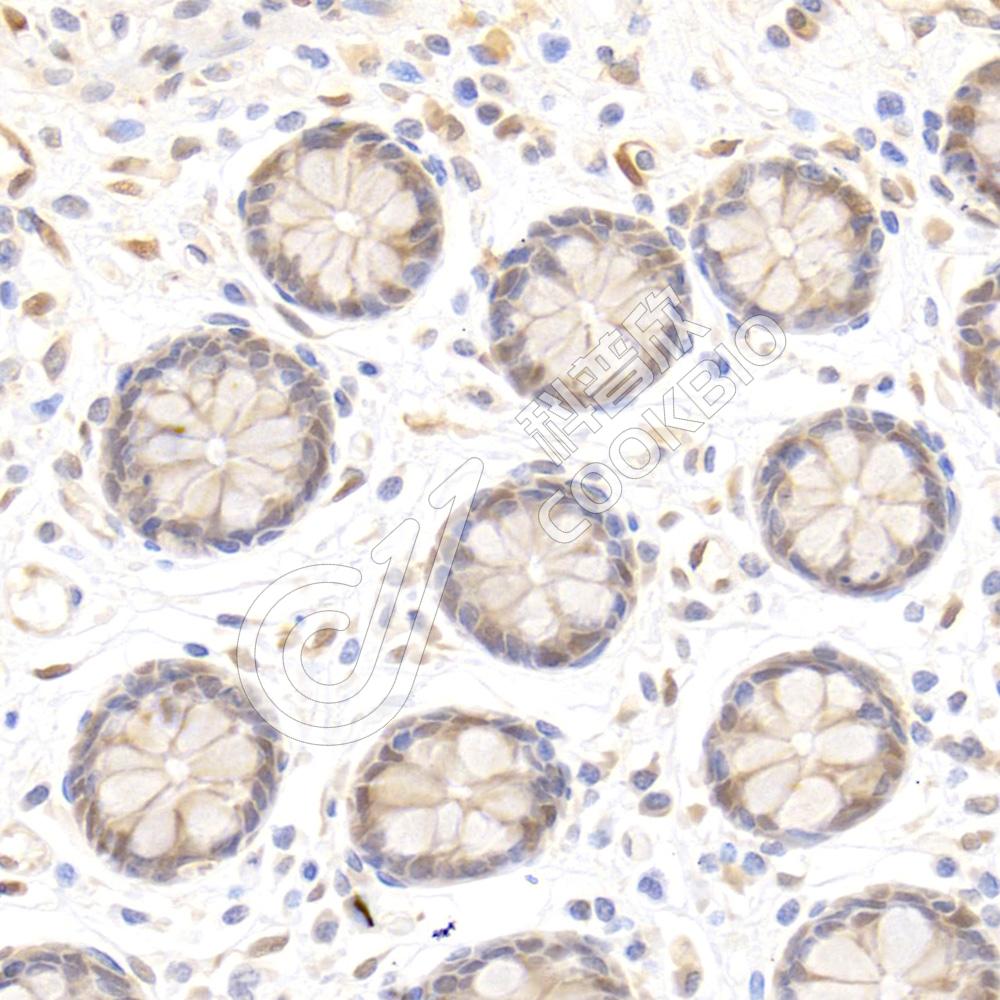

IF检测IL-2 Receptor alpha蛋白(货号 K134836)(红色).

样品: 大鼠脾, 4%多聚甲醛 (货号KSG1101) 固定12-24小时.

抗原修复: Tris-EDTA抗原修复液(pH 9.0) (KSG1203), 98℃, 20分钟.

封闭: 3% BSA(货号KSGC305010)的PBS溶液, 室温孵育30分钟.

—抗: 1: 600稀释, 4℃ 孵育过夜.

二抗: Cy3标记山羊抗兔IgG (H+L) (货号KB63909), 1: 300稀释, 室温孵育1小时.